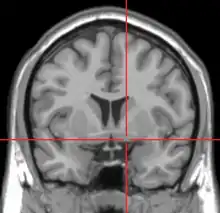

Repérage de la substance innominée de Reichert par IRM.

La substantia innominata dite aussi « substance innominée de Reichert » désigne la partie du cerveau au sein du prosencéphale basal constituée d'un ensemble mal défini de structures incluant le noyau basal de Meynert et une partie du striatopallidum ventral (dont le noyau accumbens), d'une part et une partie du complexe amygdalien d'autre part.